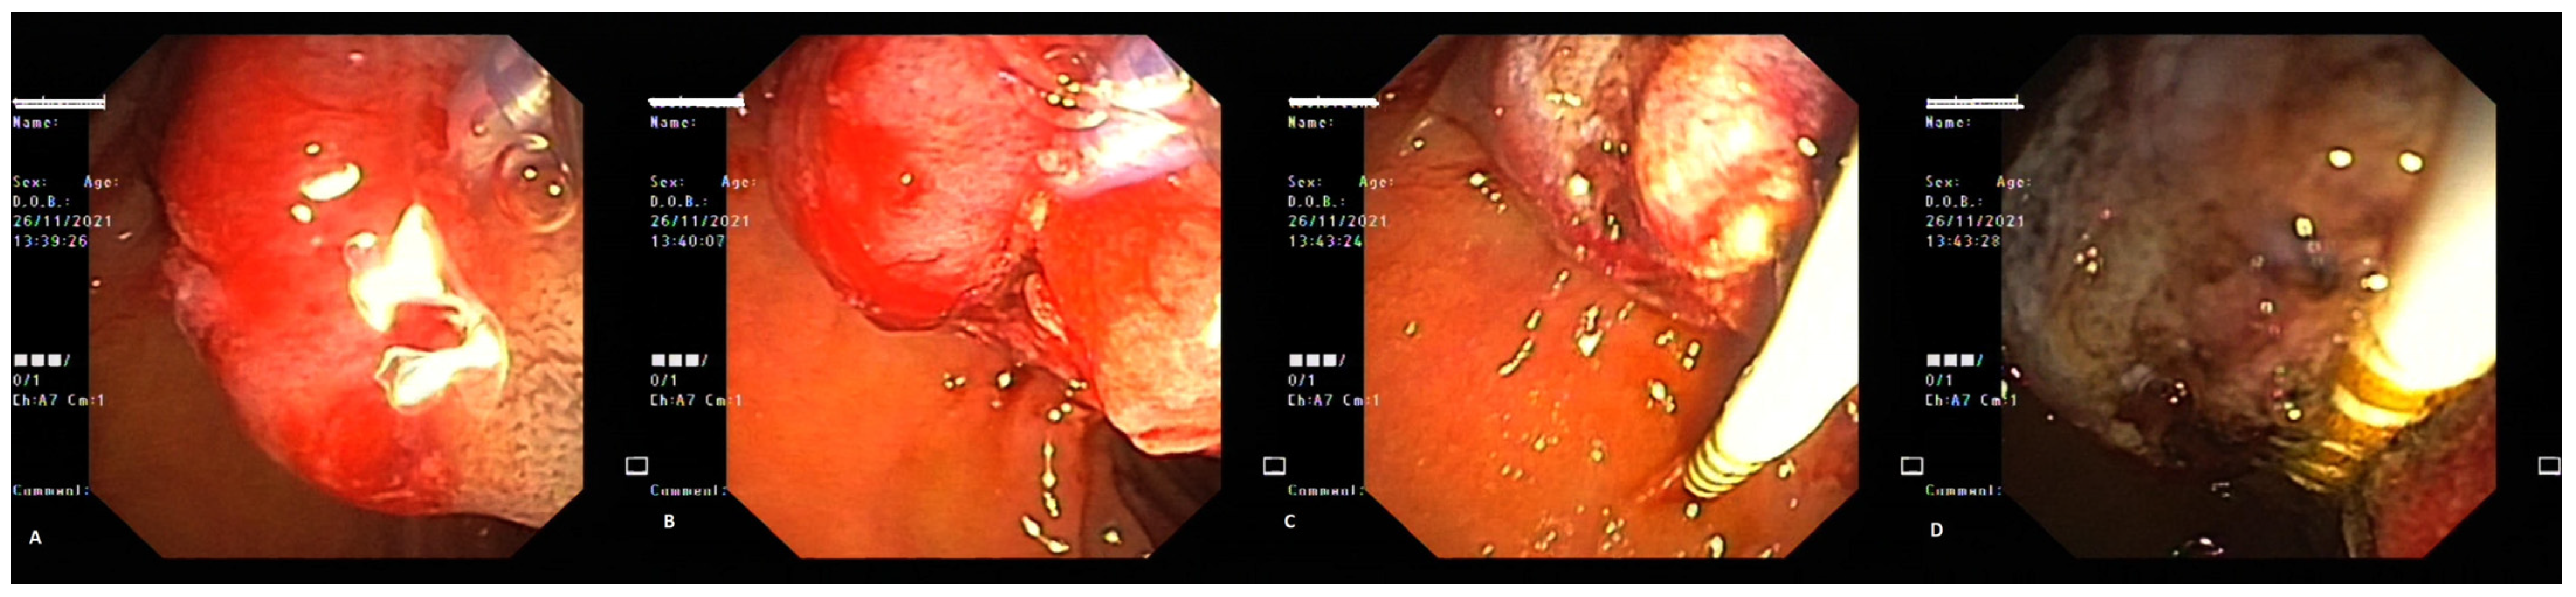

2. Case Report 1

3. Case Report 2

4. Case Report 3